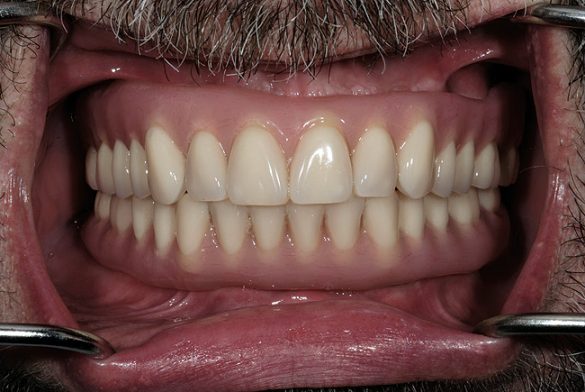

Protezele au fost prelucrate şi apoi reinserate intraoral pe schelete şi ataşamente (fig. 10, 11). S-a efectuat o înregistrare a ocluziei cu un stop de deprogramare frontal şi cazul a fost remontat pentru perfecţionarea ocluzală.

Barele s-au înşurubat pe implante şi s-au inserat protezele finale, explicând pacientului instrucţiunile aferente (fig. 12, 13).

Cunoaşterea susceptibilităţii semnificative a pacientului la boală parodontală şi conceperea planului de tratament pentru a reduce şi gestiona riscul a permis ameliorarea prognosticului pe termen lung. Extragerea tuturor dinţilor a anulat riscul biomecanic şi parodontal. Proteza sprijinită pe implante s-a conceput pentru a fi în armonie funcţională, iar riscul dentofacial a fost gestionat prin poziţionarea verticală a dinţilor din proteză mai favorabil în cadrul structurii labiale şi faciale. O revizuire sistematică a riscului şi a prognosticului a clădit bazele planului de tratament ce a oferit îmbunătăţirea semnificativă în calitatea vieţii pacientului şi a diminuat riscul problemelor dentare viitoare.